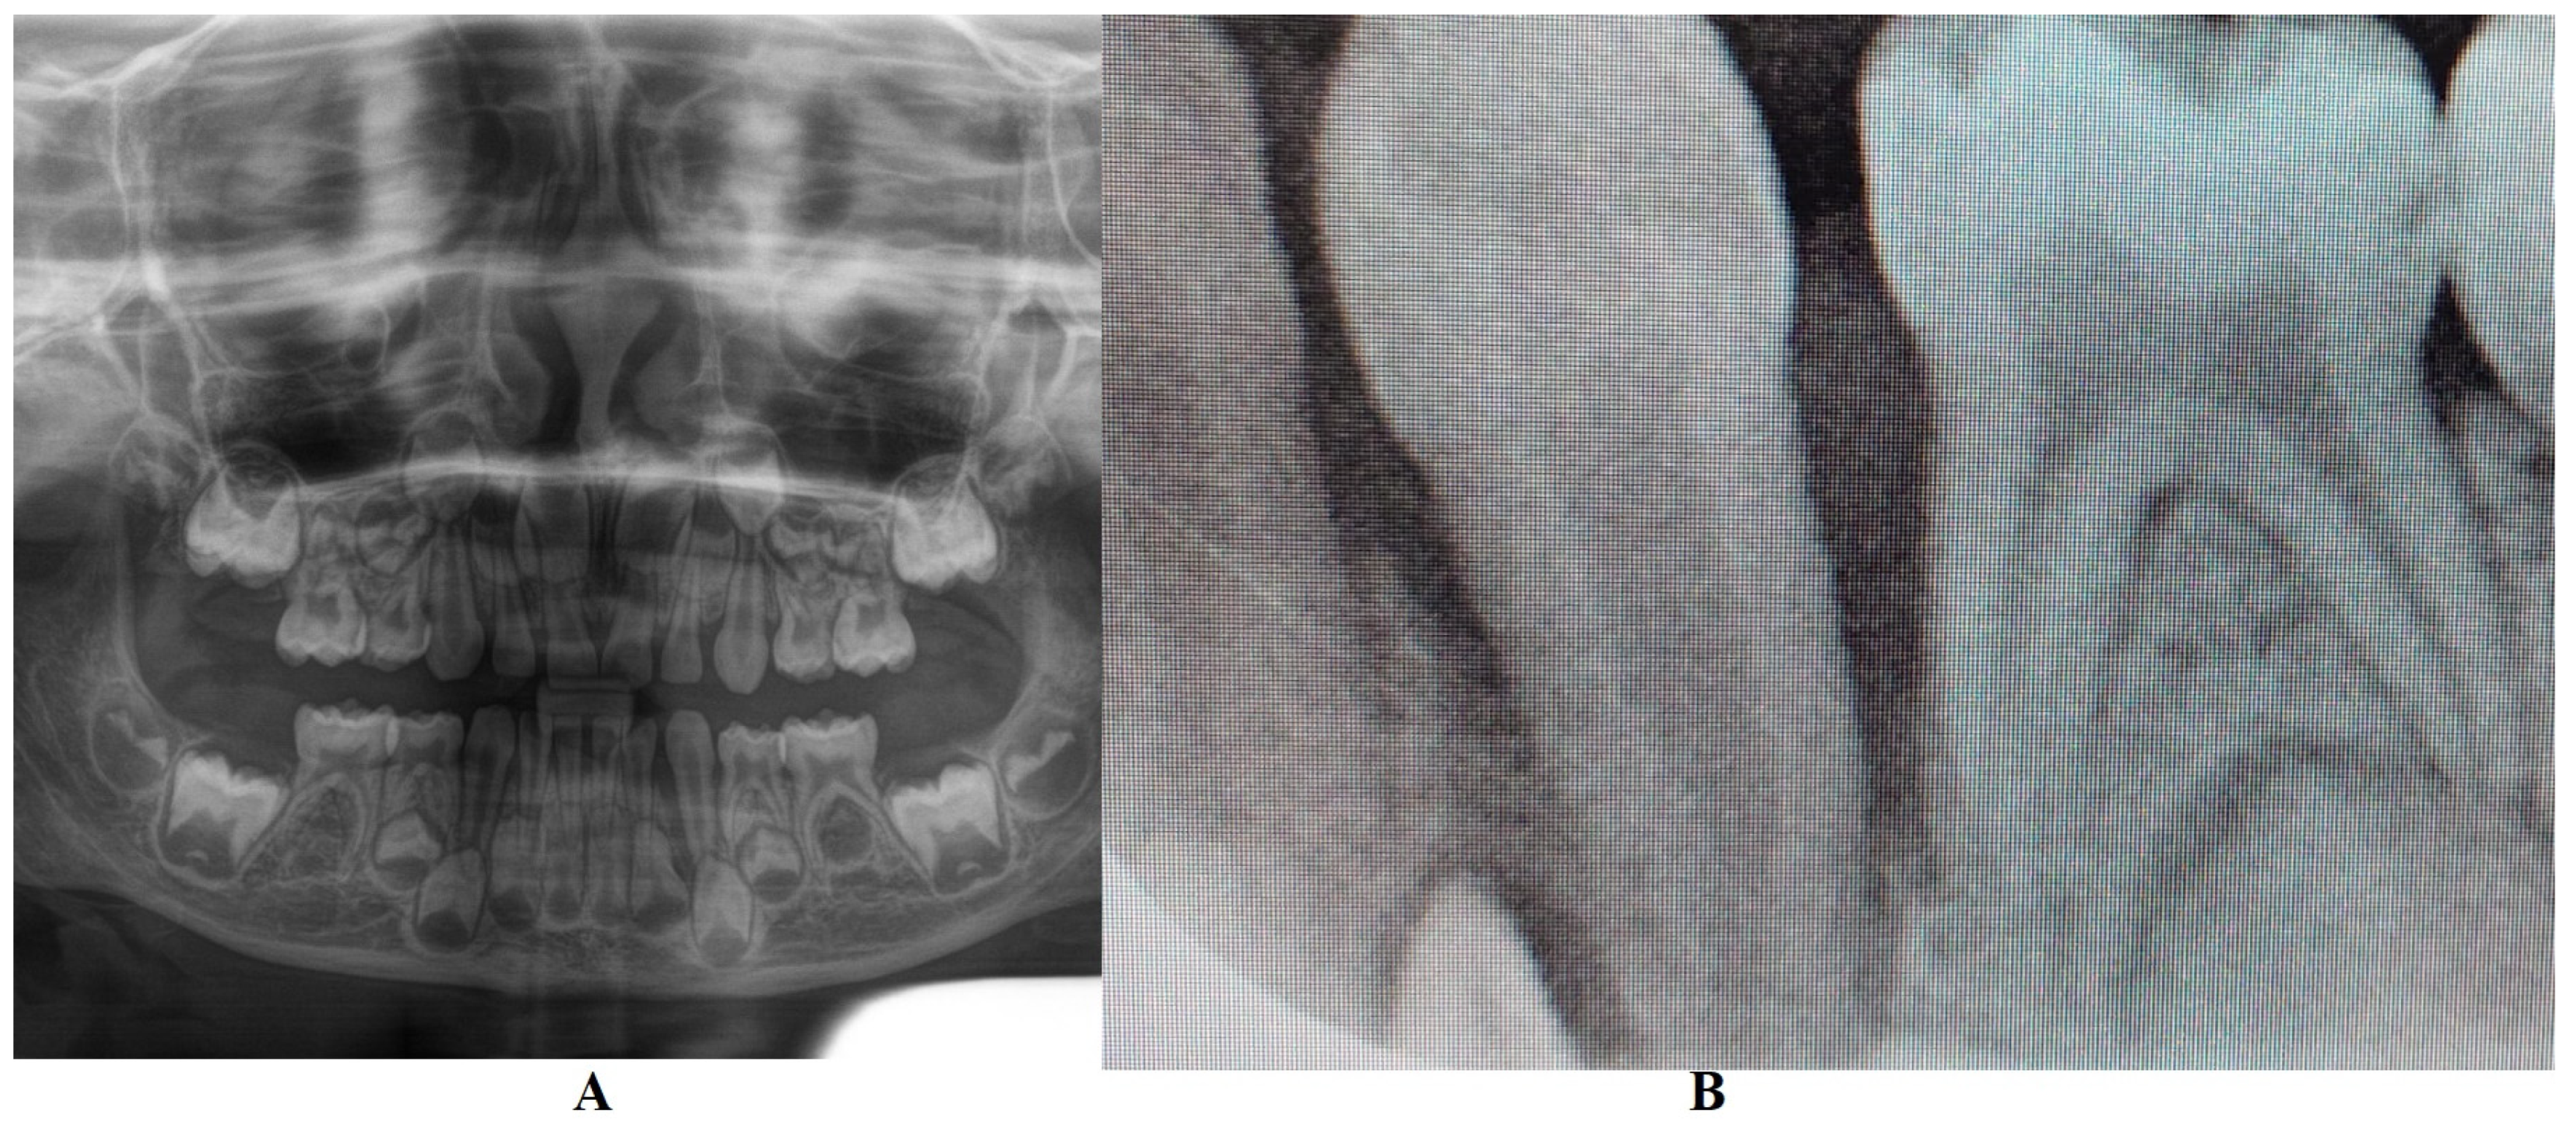

The family kept in touch with the clinician who diagnosed the LPP disorder informing them about the case evolution, and in late December 2023, the family returned to Klausenburg (Cluj-Napoca—Romania). The panoramic X-ray (Figure 3) confirmed not only the presumed advanced periodontal loss around 8.3 but also bone loss around the upper deciduous canine and incisors (i.e., 5.3, 5.2 and 5.1), when compared with the previous panoramic from June 2023 (Figure 1). Another investigated aspect was the lower left region of previous troubles, with no radiological signs of definitive canine sufferance (i.e., 3.3) and visible signs of bone regeneration. The oral clinical examination confirmed the lack of dental plaque and calculus, the advanced mobility of the deciduous lower canine, a light mobility of the other above-mentioned teeth and healing of the lost deciduous lower left canine area (Figure 4). Another periodontopathic bacterial test was taken to reflect the latest bacterial types. Nevertheless, an oral professional cleaning was performed and based on previous LPP positive diagnosis, positive periodontopathic bacterial test and clinical evolution, a systemic antibiotic treatment was prescribed. The prescribed antibiotic (girl’s weight was about 15 kg) association was of Augmentin of 500 mg (1 g/day, 1 table twice a day) and Metronidazole of 250 mg (500 mg/day, 1 tablet twice a day, but with the need to adjust the dosage if allergy/overdose signs were to be displayed) for a period of 10 days and a periodontopathic bacterial test 2–3 months after the treatment ceased.

The periodontopathic bacterial test taken before the antibiotic prescription (i.e., late December 2023) was highly positive with five types of bacteria (when compared with only two types in the previous test received 16 August 2023). Thus, besides the two types present in first test (i.e., 16 August 2023), Fusobacterium nucleatum/periodonticum and Capnocytophaga already present in the oral cavity (and responsible for the loss of 7.3 and localized periodontal destruction), remaining highly positive, another three types showed up mildly positive: Treponema denticola, Eubacterium nodatum and Eikenella corrodens, confirming not only the clinical worsening of the oral condition (Figure 3 and Figure 4) seen during oral examination (late December 2023) but also the chosen antibiotic association scheme.

The unusualness of this case is due to several aspects. The first is related to the extremely young age of the patient (i.e., 4 years old in February 2023, deciduous dentition), with an insidious onset, and apparently no familial aggregation or history. The second aspect is related to the misdiagnosis of metabolic diseases (i.e., hypophosphatasia/hyperphosphatasia as written) with oral manifestations (since no therapeutic measures were taken) despite the initial radiographical (i.e., Figure 1) and clinical examination that suggested a clear picture of an unusual LPP (e.g., the lower left canine involvement). The third aspect is related to the lack of therapeutic measures that rapidly set the course for the periodontal and 7.3 loss, in an interval of around 7 months (Figure 2) and the further progression involving other oral sites (Figure 3 and Figure 4). The fourth aspect is related to the evolution under adequate treatment (despite no written report to guide it) and the periodontal gain over a period of around 8 months following the antibiotic therapy (Figure 5 and Figure 6).

The natural periodontal gain observed in this case is important from the prognosis point of view. It was observed that the site of the lost 7.3 showed periodontal gain (i.e., Figure 3, the panoramic form early January 2024), in the absence of the correct antibiotic association (since solely Augmentin did not cover all pathological bacterial types). However, it must be emphasized that one cannot predict the impact on this matter of the above-mentioned incorrect antibiotic treatment performed in October 2023 (i.e., no signs of other periodontal gain on the upper and lower incisors and only progression of the periodontal loss around the 8.3). Nevertheless, significant periodontal gain was observed on the last panoramic (Figure 6, May 2024) after the correct antibiotic association.

Figure 3. Panoramic X-ray radiological investigations with advanced periodontal loss around the deciduous lower right canine, and periodontal gain around deciduous lower left canine site (late December 2023) (Klausenburg, Romania).